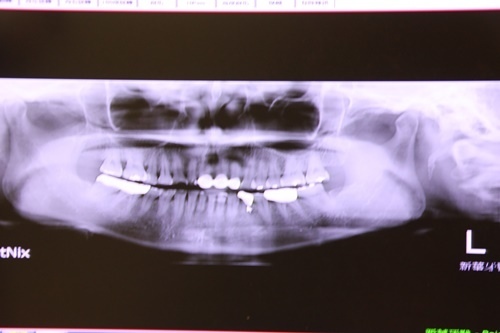

↑↑假牙尚未更換治療前 ↑↑

因為有磨牙習慣她的牙齒被磨得很小顆幾乎已經傷到牙神經

為保留下這幾顆牙齒她就做了假牙牙套套著做保護

長年累月下來她的固定式假牙已經慢慢變質

從牙齦萎縮跟金屬牙套之間也冒出來空洞